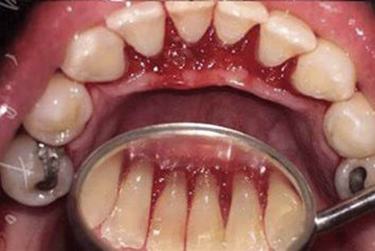

- Bleeding or swollen gums

- Prevents gum disease

- Reduces bleeding gums

- Promotes healthy gums